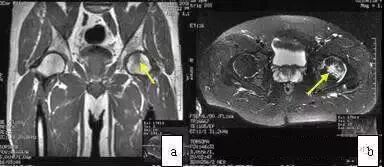

MRI的T1WI为弥散低信号,T2WI为高信号,范围累及整个股骨头、颈,甚至扩展至大转子(图4)。与ONFH不同的是ITOH无低信号带和双线征。X线片显示转子部骨量减少,因此鉴别不难。ITOH为自限性疾病,经非手术治疗4月~1年可完全恢复,包括MRI图像。

图4 女,45岁,突发性左髋疼痛,无诱因,诊断为暂时性骨质疏松症。(a)T2WI示股骨头颈及转子间弥散性高信号(冠状位);(b)T2WI示股骨头高信号(轴位);(c)T1WI示股骨头低信号;(d)X线片示股骨头颈及转子部骨量减少